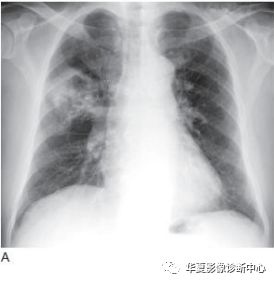

影像学表现常见息肉状腔内肿块和(或)支气管阻塞(图1A)。肺门的肿块也很常见,这归因于肿瘤位于中心位置,可侵犯局部组织,累及肺门淋巴结(图1B)。肺不张(图2)实变、黏液嵌塞和支气管扩张常见,提示支气管阻塞。只有30%的鳞癌表现为肺外围结节。中央坏死和空洞(图3)较其他类型肺癌更常见。

图1 表现为支气管腔内和肺门肿块的鳞状细胞癌

A.CT 显示右下叶支气管内息肉状的肿块(箭头),为典型的鳞状细胞癌;B.在稍低层面,支气管腔阻塞伴局部浸润,导致肺门肿块(M)。